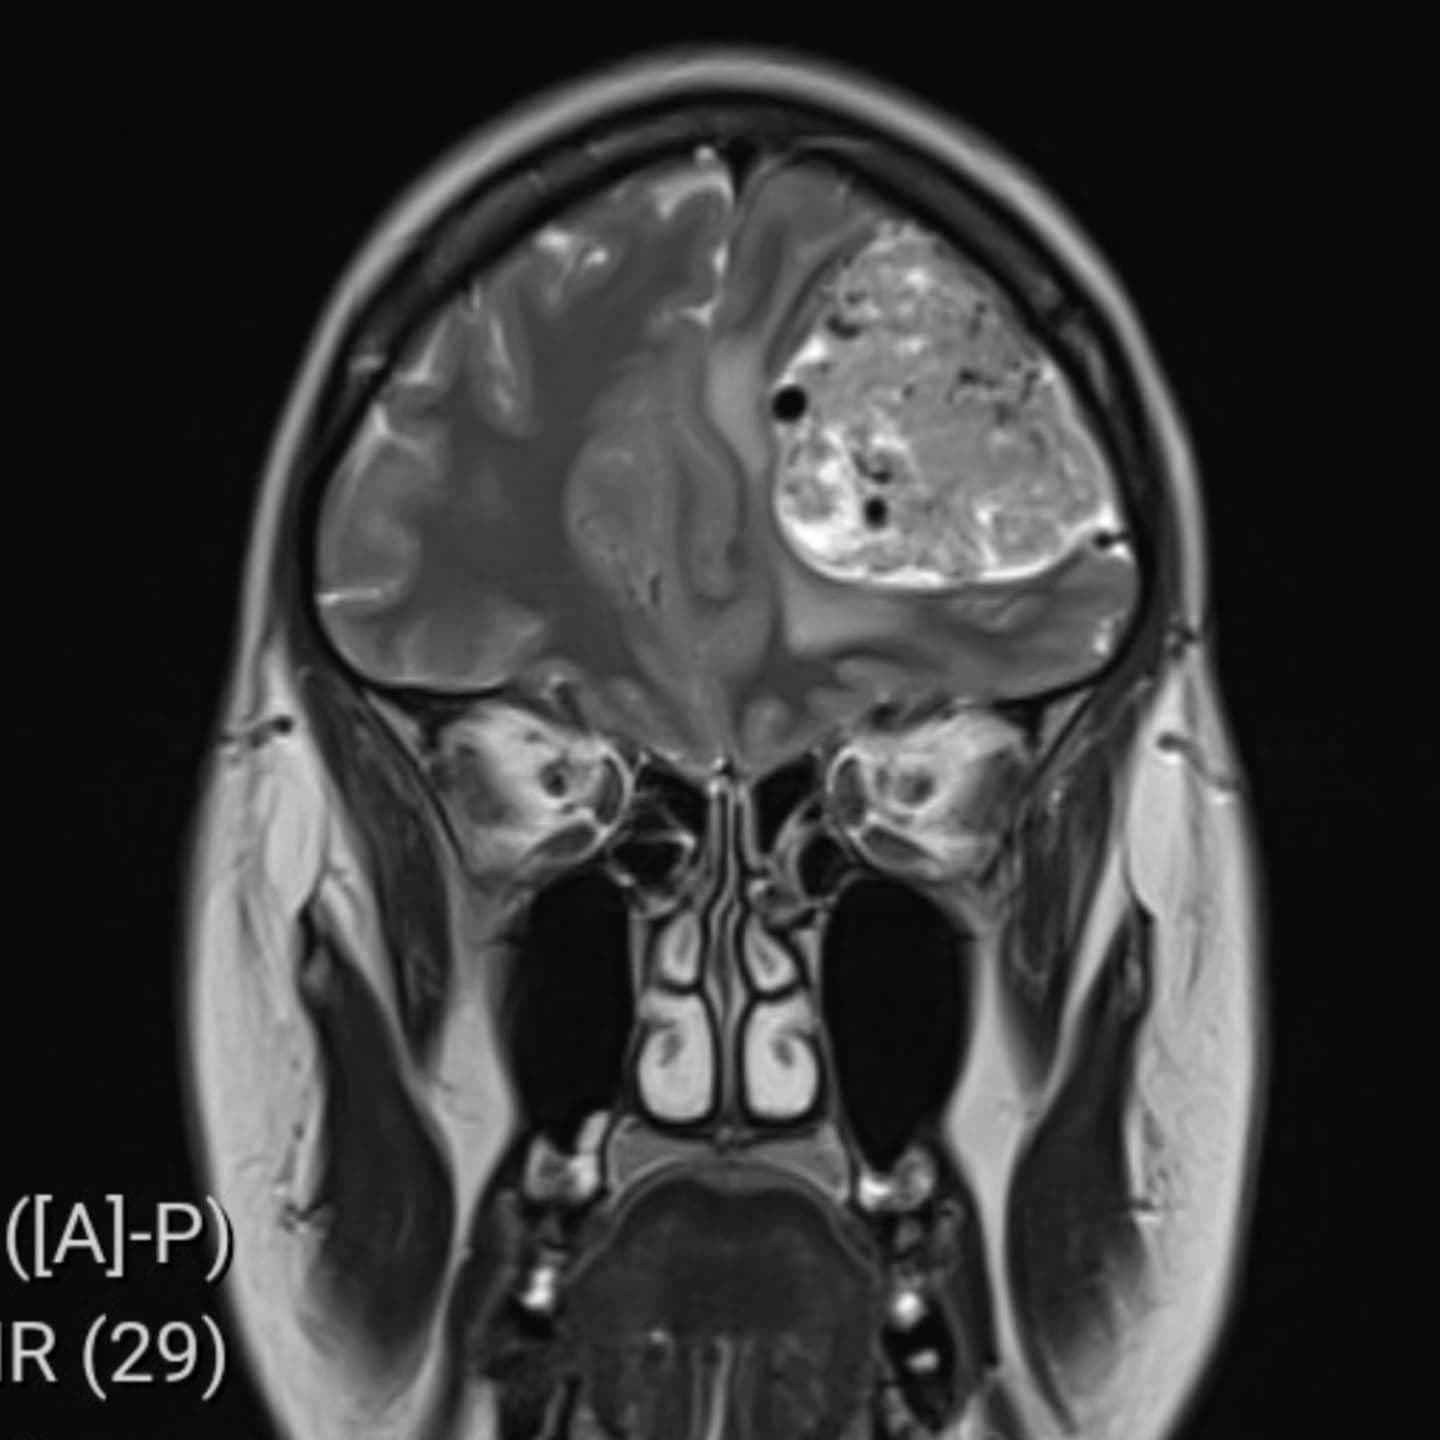

Šokujúca diagnóza

Výsledok prišiel už o pár hodín. Lekári ju okamžite poslali na urgentné oddelenie nemocnice v Medway, kde jej diagnostikovali rozsiahlu masu v čelovom laloku. Neskôr sa potvrdilo, že ide o meningeóm – nezhubný nádor mozgu. „Zrútila som sa, keď mi to povedali. Dlho trvalo, kým som sa vôbec dostala k správnej diagnóze,“ uviedla Nikita. V apríli 2025 podstúpila na londýnskej klinike King’s College Hospital štvorhodinovú operáciu, počas ktorej jej lekári nádor úplne odstránili. Zákrok prebehol práve v deň 40. narodenín jej manžela. „Ja som bola pokojná, ale pre rodinu to bolo omnoho ťažšie,“ dodala.